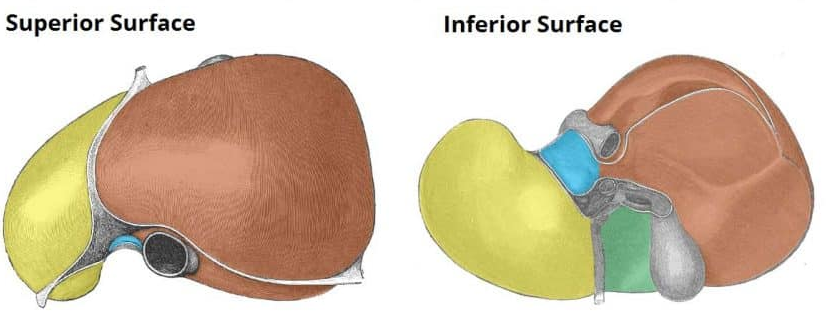

Right liver lobe

orange highlight

Left liver lobe

yellow highlight

Falciform ligament

Coronary ligament

Round ligament

Caudate lobe

blue highlight

Quadrate lobe

green highlight

Porta hepatis

What do all these make up (this is the posterior liver)

Inferior vena cava

Hepatic artery

Hepatic portal vein